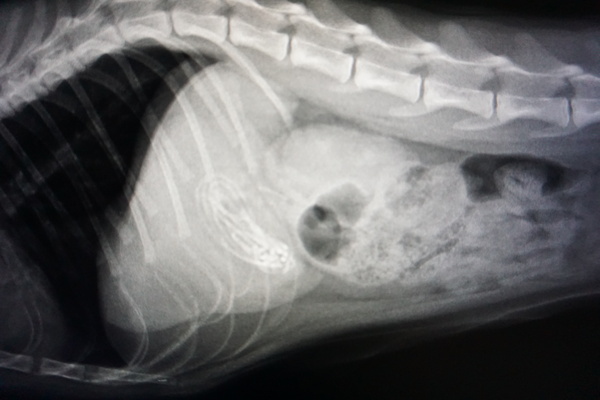

今回は、レントゲンではっきりとひも状異物がうつり、胃内には他にフードもなかったので、内視鏡にて取り出すことができました

ひも状異物は胃から腸へすすむと腸閉塞をおこしやすく、とても危険です